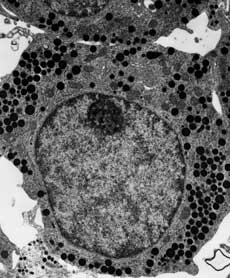

There are two main types of electron microscope – the transmission EM (TEM) and the scanning EM (SEM). The transmission electron microscope is used to view thin specimens (tissue sections, molecules, etc) through which electrons can pass generating a projection image. The TEM is analogous in many ways to the conventional (compound) light microscope. TEM is used, among other things, to image the interior of cells (in thin sections), the structure of protein molecules (contrasted by metal shadowing), the organization of molecules in viruses and cytoskeletal filaments (prepared by the negative staining technique), and the arrangement of protein molecules in cell membranes (by freeze-fracture).